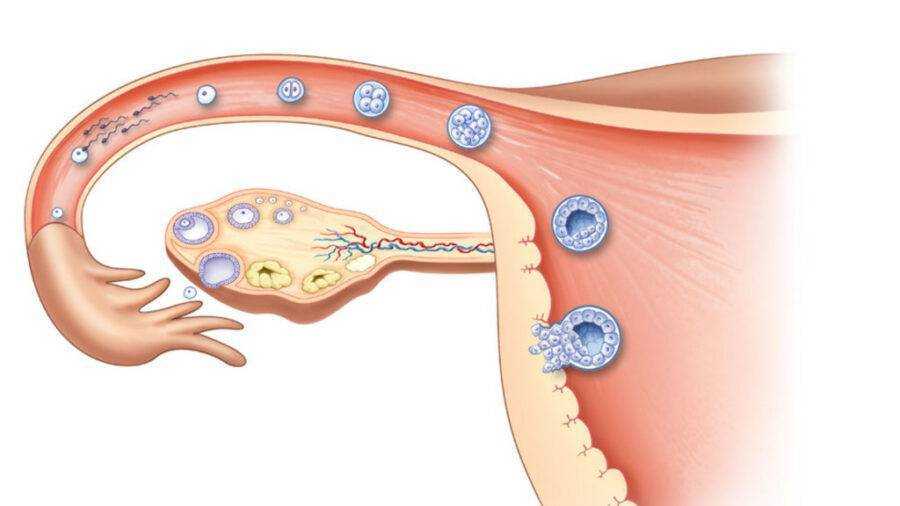

Созревание фолликула в яичнике: этапы и процессы